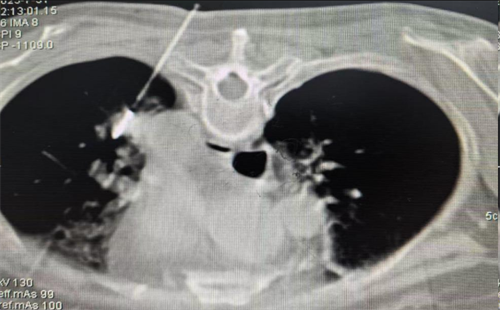

术中精准定位肺转移瘤位置

微波消融技术是指在CT或超声引导下进行局部麻醉,将仅2毫米的消融针精准穿刺至肿瘤内部。针尖释放的微波能量可在60秒内将局部温度升至80-120℃,通过高温使癌细胞蛋白质变性坏死,但对周围健康组织的影响非常小,可以提高患者机体的免疫力,抑制肿瘤细胞的扩散。